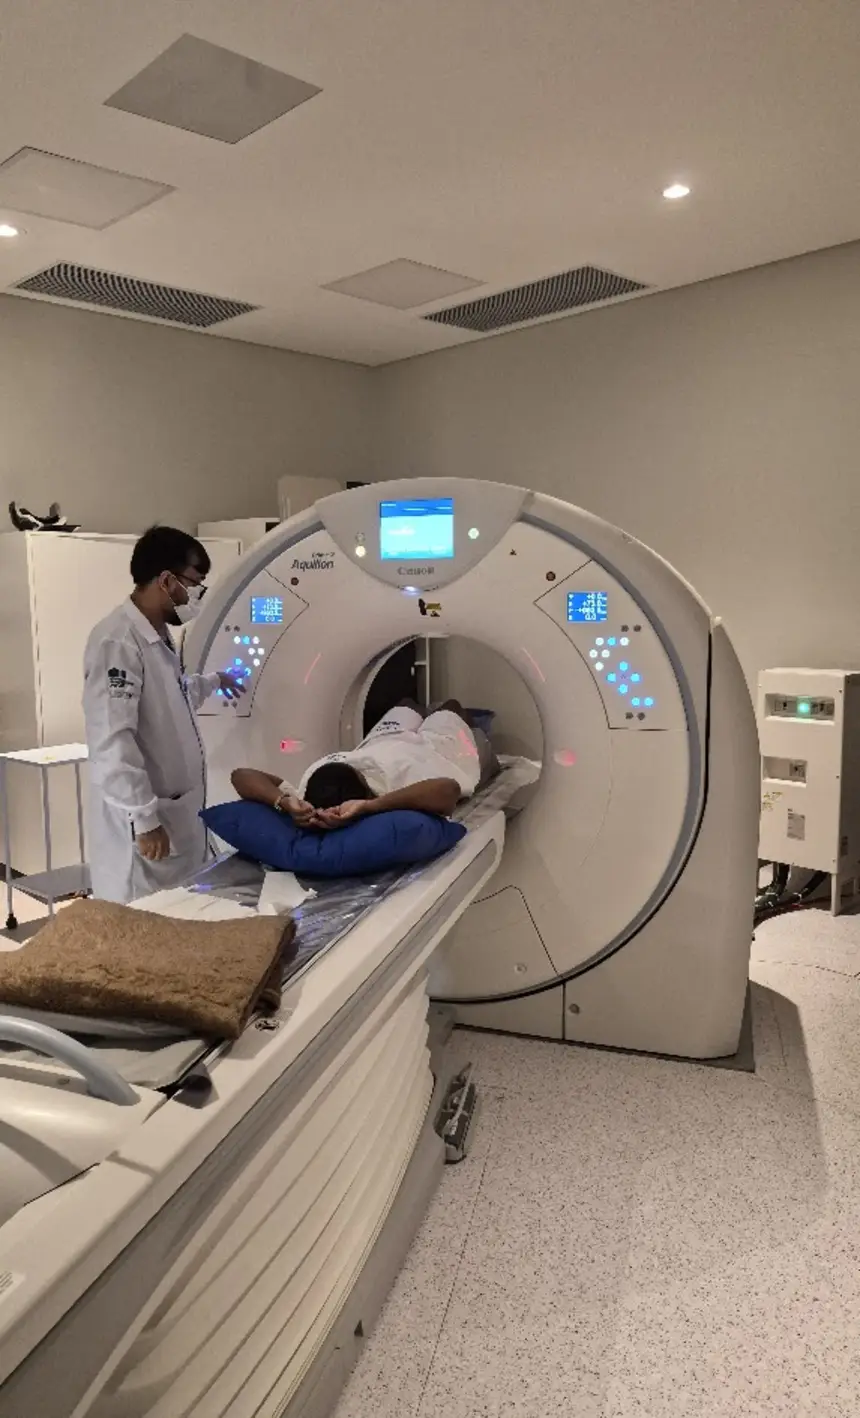

A usuária do SUS Emilly Nicoly Costa Soares foi uma das primeiras a utilizar o novo equipamento de tomografia.

“Foi muito bom estrear o equipamento, porque eu estava esperando há muito tempo. Meu marido está me acompanhando e sabe o quanto foi difícil conseguir. Agora deu tudo certo, graças a Deus. Foi um sucesso. O ambiente é frio, mas faz parte”, relatou a paciente.

O Centro Tecnológico é composto por aparelhos de ressonância magnética, tomógrafo computadorizado, equipamento de mamografia, raio X telecomandado e densitometria óssea.

Os equipamentos foram adquiridos por meio de contratação e fazem parte do plano de qualificação de exames por imagem.